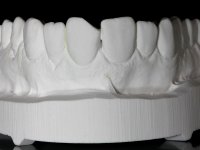

Paciente do sexo feminino, com 27 anos, não fumadora, apresentava uma restauração com resina composta tipo “Classe IV”, no angulo mesial do dente 2.1. A restauração não satisfazia esteticamente e fraturava com frequência. O bordo incisal do incisivo central direito e o remanescente natural do incisivo central esquerdo apresentava uma caracterização bastante marcada. Várias áreas de translucidez que tornariam a reabilitação bastante exigente sobre o ponto de vista técnico e estético. Na área da fratura não havia dentina exposta. A paciente gostava que a reabilitação tivesse uma abordagem o mais conservadora possível.

Realizou-se uma pré impressão em silicone para posteriormente ser feita uma restauração provisória em resina composta de polimerização “dual”. Seguidamente foi removida toda a restauração e realizado o preparo dentário. Este preparo consistiu na planificação do angulo dentário e na preparação ligeira da superfície palatina. A superfície palatina foi preparada para um assentamento sem interferências. Foi realizada uma impressão com dupla mistura e dupla viscosidade e de seguida foi feita uma restauração provisória em resina de polimerização “dual” sem qualquer tipo de adesão. Em laboratório, realizado o modelo de trabalho foi confecionada uma micro restauração de cerâmica feldespática. Essa peça de cerâmica utilizou essencialmente a superfície palatina mesial e o angulo incisal para se estabilizar. Na superfície vestibular a peça de cerâmica sobrepunha-se á superfície vestibular dentária em cerca de 2mm. Na clínica, a restauração provisória foi removida. A superfície dentária foi devidamente preparada e a micro restauração cerâmica depois de devidamente acondicionada foi colada no dente somente com adesivo. A superfície de cerâmica que sobrepunha a superfície dentária vestibular foi cuidadosamente eliminada. Para isso foi sendo feito o seu polimento de forma progressiva com discos e pontas de borracha.